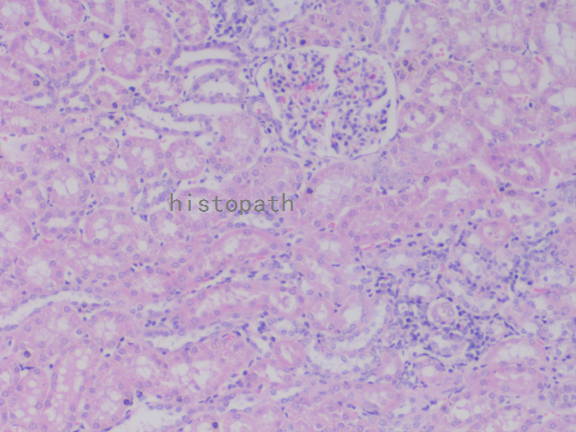

苏木精--伊红染色法(hematoxylin-eosin staining),简称HE染色法,石蜡切片技术里常用的染色法之一。苏木精染液为碱性,主要使细胞核内的染色质与胞质内的核酸着紫蓝色;伊红为酸性染料,主要使细胞质和细胞外基质中的成分着红色。HE染色法使组织学、胚胎学、病理学教学与科研中最基本、使用最广泛的技术方法。

染色结果:

细胞核呈蓝色,细胞质、肌肉、结缔组织、红细胞、嗜曙红颗粒呈不同程度的粉红色。钙盐、软骨基质和各种微生物也可染成蓝色或紫蓝色。核仁呈红色。着色情况不仅与组织或细胞的种类有关,也随其生活周期及病理变化而改变。质量优良的HE染色切片样本,细胞核与细胞质蓝红对比明显,胞核鲜明,核膜及核染色质颗粒均清晰可见。